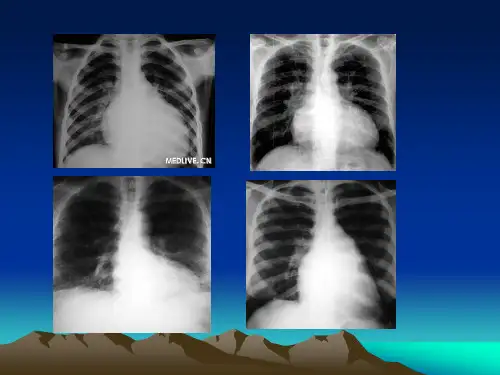

1.左心室增大心左界向左下扩大,心腰加深近似直角,心浊音界呈靴形。

因最常见于主动脉瓣关闭不全,故又称主动脉型心脏。

也可见于高血压性心脏病。

高血压性心脏病

2.右心室增大轻度增大时,只使心绝对浊音界增大,心左界叩诊不增大。

显著增大时,相对浊音界向左右扩大,但因心脏长轴发生顺钟向转位,故向左增大较为明显,浊音界不向下扩大。

常见于肺心病、单纯二尖瓣狭窄等。

3.双心室增大心浊音界向两侧扩大,且左界向下扩大,称普大型心脏。

常见于扩张型心肌病、克山病、重症心肌炎、全心衰竭等。

心肌病

4.左心房增大显著增大时,胸骨左缘第3肋间心浊音界向外扩大。

5.左心房及肺动脉扩大胸骨左缘第2、3肋间心浊音界向外扩大。

心腰饱满或膨出,心浊音界如梨形,因常见于二尖瓣狭窄,故又称二尖瓣型心脏。

二尖瓣狭窄型心脏

6.主动脉扩张及升主动脉瘤第1、2肋间浊音区增宽。

7.心包积液坐位时心浊音界呈三角形(烧瓶形),仰卧位时心底部浊音区增宽,这种随体位改变而变化的心浊音界是心包积液的典型体征。

心包积液

8.大量胸腔积液、积气时,心界在患侧叩不出,健侧心浊音界向外移。

肺实变、肺肿瘤或纵隔淋巴结肿大时,如与心浊音界重叠则心界叩不出。

肺气肿时,心浊音界变小,甚至叩不出。

9.大量腹腔积液或腹腔巨大肿瘤,使膈升高,心脏横位,叩诊时心界扩大。

镜面右位心时,可在胸骨右侧相应位置叩出心浊音界。

右位心。